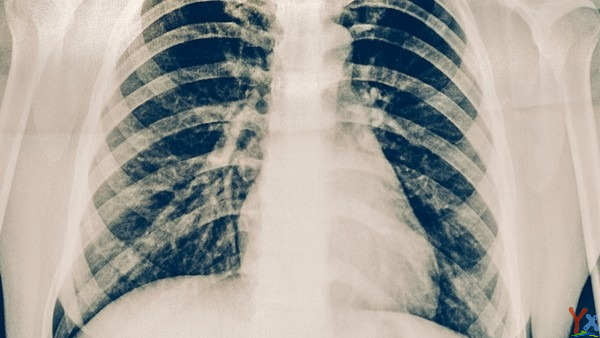

近期,儿童支原体肺炎颇受家长关注,有家长担心孩子感染肺炎支原体后会得肺炎,出现白肺。对此,北京儿童医院重症医学科主任王荃表示,不是所有的支原体感染都会发展为肺炎,因为绝大多数孩子都属于轻症,没有出现支原体肺炎。只有肺炎支原体侵入人的下呼吸道,才可能出现支原体肺炎。

而“白肺”的症状和严重程度都与支原体肺炎不同。有的支原体肺炎患儿,肺部影像上显示有一片白色,大多是一个肺叶或一个肺段感染所致,主要是由于气道阻塞物或肺内炎性渗出引起的,但其他的肺叶大多都是正常的,并不是医学上所说的“白肺”。